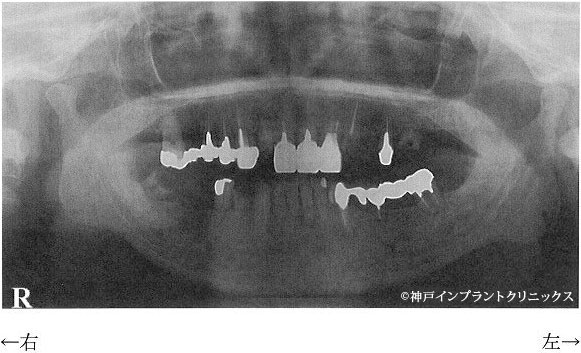

●パノラマレントゲン写真

現在の状態

今回左下の奥歯の件でお越しいただきましたか、右下奥にも大きな病巣があります。

順次治療か必要です。

まず右下の7番目と左下の6番目の抜歯が必要です。

インプラント治療の際、抜歯即時インプラントといって抜歯後すぐにインプラントを入れる方法を取ることもありますが、今回の歯の状態は細菌による感染が大きくその適応ではありません。

抜歯した部分は徐々に歯ぐきや骨が回復していきます。およそ3ヵ月〜6ヵ月が目安となりますが、それより早くにインプラントを埋める事が出来る場合もあります。

左下5番目の歯は根尖病巣(根の先の細菌による病巣)があります。

CT画像から判断すると古い薬か器具の一部が影響して病巣を引き起こしている可能性もあります。

根の治療がうまくいけば土台を立てて被せる方法を取りますが、場合によっては抜歯になる可能性もあります。